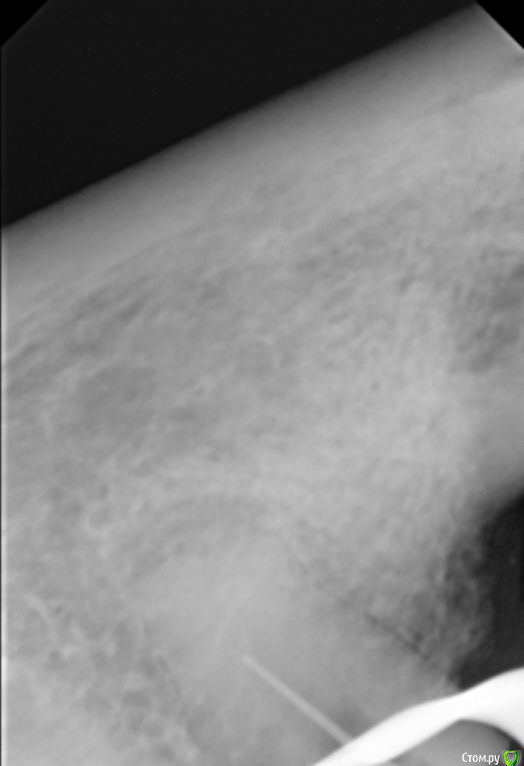

Елена509 Опубликовано 19 ноября, 2015 Поделиться Опубликовано 19 ноября, 2015 Доктора, помогите, пжл, ситуация какая - ортопед направил для удаления штифта и перепломбирования к.к 35, начали - анестезия, выудили штифт, начали расширять, уперлись на 15 мм, пошли на снимок с гутт штифтом(прилагается), недолет, вернулись, сразу прошли дальше, по апексу -18мм, убавила до 17,5, мастер штифт - 35, латералка, пошли на контроль, а там - загнутый штифт за верхушкой(рг прилагается), вернулись, все вытащила, загнутый тоже(95% - я его прям признала), отмыли просушили, по апексу те же 18мм, примеряю мастер штифты все как то не так встает, в итоге 70 подогнала, на те же 17,5 мм, поставила, с латералкой, идем на контроль, там вот такая вот фигня(рг - "последний"), вопросы - это что, невытащеннный гут.штифт или на его место эпоксидка затекла? что с прогнозом и что делать? 1 Ссылка на комментарий

Сева северный Опубликовано 19 ноября, 2015 Поделиться Опубликовано 19 ноября, 2015 (изменено) перед тем, как пошли делать с гут.штифтом рг недолет показывал, вроде нормально все было, когда пломбировали, штифты тоже никуда не уходили на месте стояли, я даже как то растерялась сильно, когда на контрольном на столько за апекс ушлисудя по фото....зуб резарцинен..... с дефектом твердых тканей( это диазноз)..ферол наверное отсутствует. Чтобы было понятно ......лечение резарциненого зуба с таким разрушением..+ осложненным необходимостью эндолечения .... является альтернативой удалению.Что касается :Что за верхушкой ?.... Границы четкие, если вынули гуту ....крючком.... для себя считайте силер..даже если и гута связь с каналом зуба отсутствует. поэтому реакция будет либо незначительная , либо отсутствовать вообще. Прогноз по зубу, строил бы из ортопедической целесообразности.... Изменено 19 ноября, 2015 пользователем Сева северный 1 Ссылка на комментарий

Л Ю С Я Опубликовано 20 ноября, 2015 Поделиться Опубликовано 20 ноября, 2015 Здесь явная резорбция апекса, поэтому локатор мог показывать неправильно. В таких случаях делайте снимок с финишным файлом, где он? Ориентируйтесь больше на рентгенологическую длину, после лечения может произойти ещё небольшая убыль апекса, поэтому пакуйте -0,5, лучше мта. Какой билдап планируется в зубе? И вообще надо рассматривать картину восстановления окклюзии в целом 1 Ссылка на комментарий

Sampson Опубликовано 21 ноября, 2015 Поделиться Опубликовано 21 ноября, 2015 Резорциненный+пародонтитный+ изменения апекальной трети корня+ тень материала за верхушкой = Я бы зуб пока сохранил в целях наблюдения. и раз в неделю проводил перкуссию. При положительной динамике отправил к ортопеду. При отрицательной к хирургу. Ссылка на комментарий